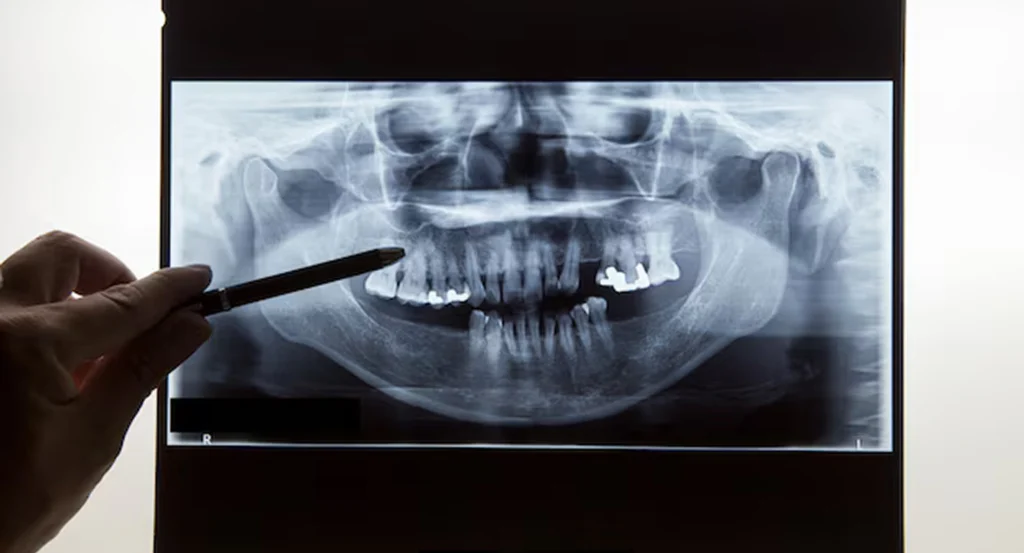

In many places, implants are still placed using only 2D X‑rays and the dentist’s feel for the bone. It can work, but there’s always some uncertainty about exactly how much bone is available, where the nerve runs or how close the sinus is.

With CBCT‑guided implants, we remove that uncertainty.

At Gelos Dentistry, we start with an in‑house 3D CBCT scan. This gives us a clear, three‑dimensional view of your jaws – bone height, width, density, nerve canals, sinus spaces – everything we need to see before touching the bone. On a computer, we then plan where each implant should go, at what angle, and to what depth.